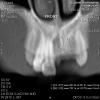

Vasyaka Опубликовано 27 ноября, 2009 Автор Поделиться Опубликовано 27 ноября, 2009 (изменено) Снимок! Изменено 27 ноября, 2009 пользователем Vasyaka Ссылка на комментарий

Bier Опубликовано 27 ноября, 2009 Поделиться Опубликовано 27 ноября, 2009 вид сверху еще покажитенедостаточно места между имплантатами у вас. от того и с сосочками проблемы. Ссылка на комментарий

Sahan Опубликовано 27 ноября, 2009 Поделиться Опубликовано 27 ноября, 2009 вид сверху еще покажитенедостаточно места между имплантатами у вас. от того и с сосочками проблемы.+1 Ссылка на комментарий

Vasyaka Опубликовано 30 ноября, 2009 Автор Поделиться Опубликовано 30 ноября, 2009 Вот здесь полная КТ:part01.rarpart02.rarpart03.rarpart04.rarмне уже "намекали" на то, что между имплантов мало места.... что делать? Ссылка на комментарий